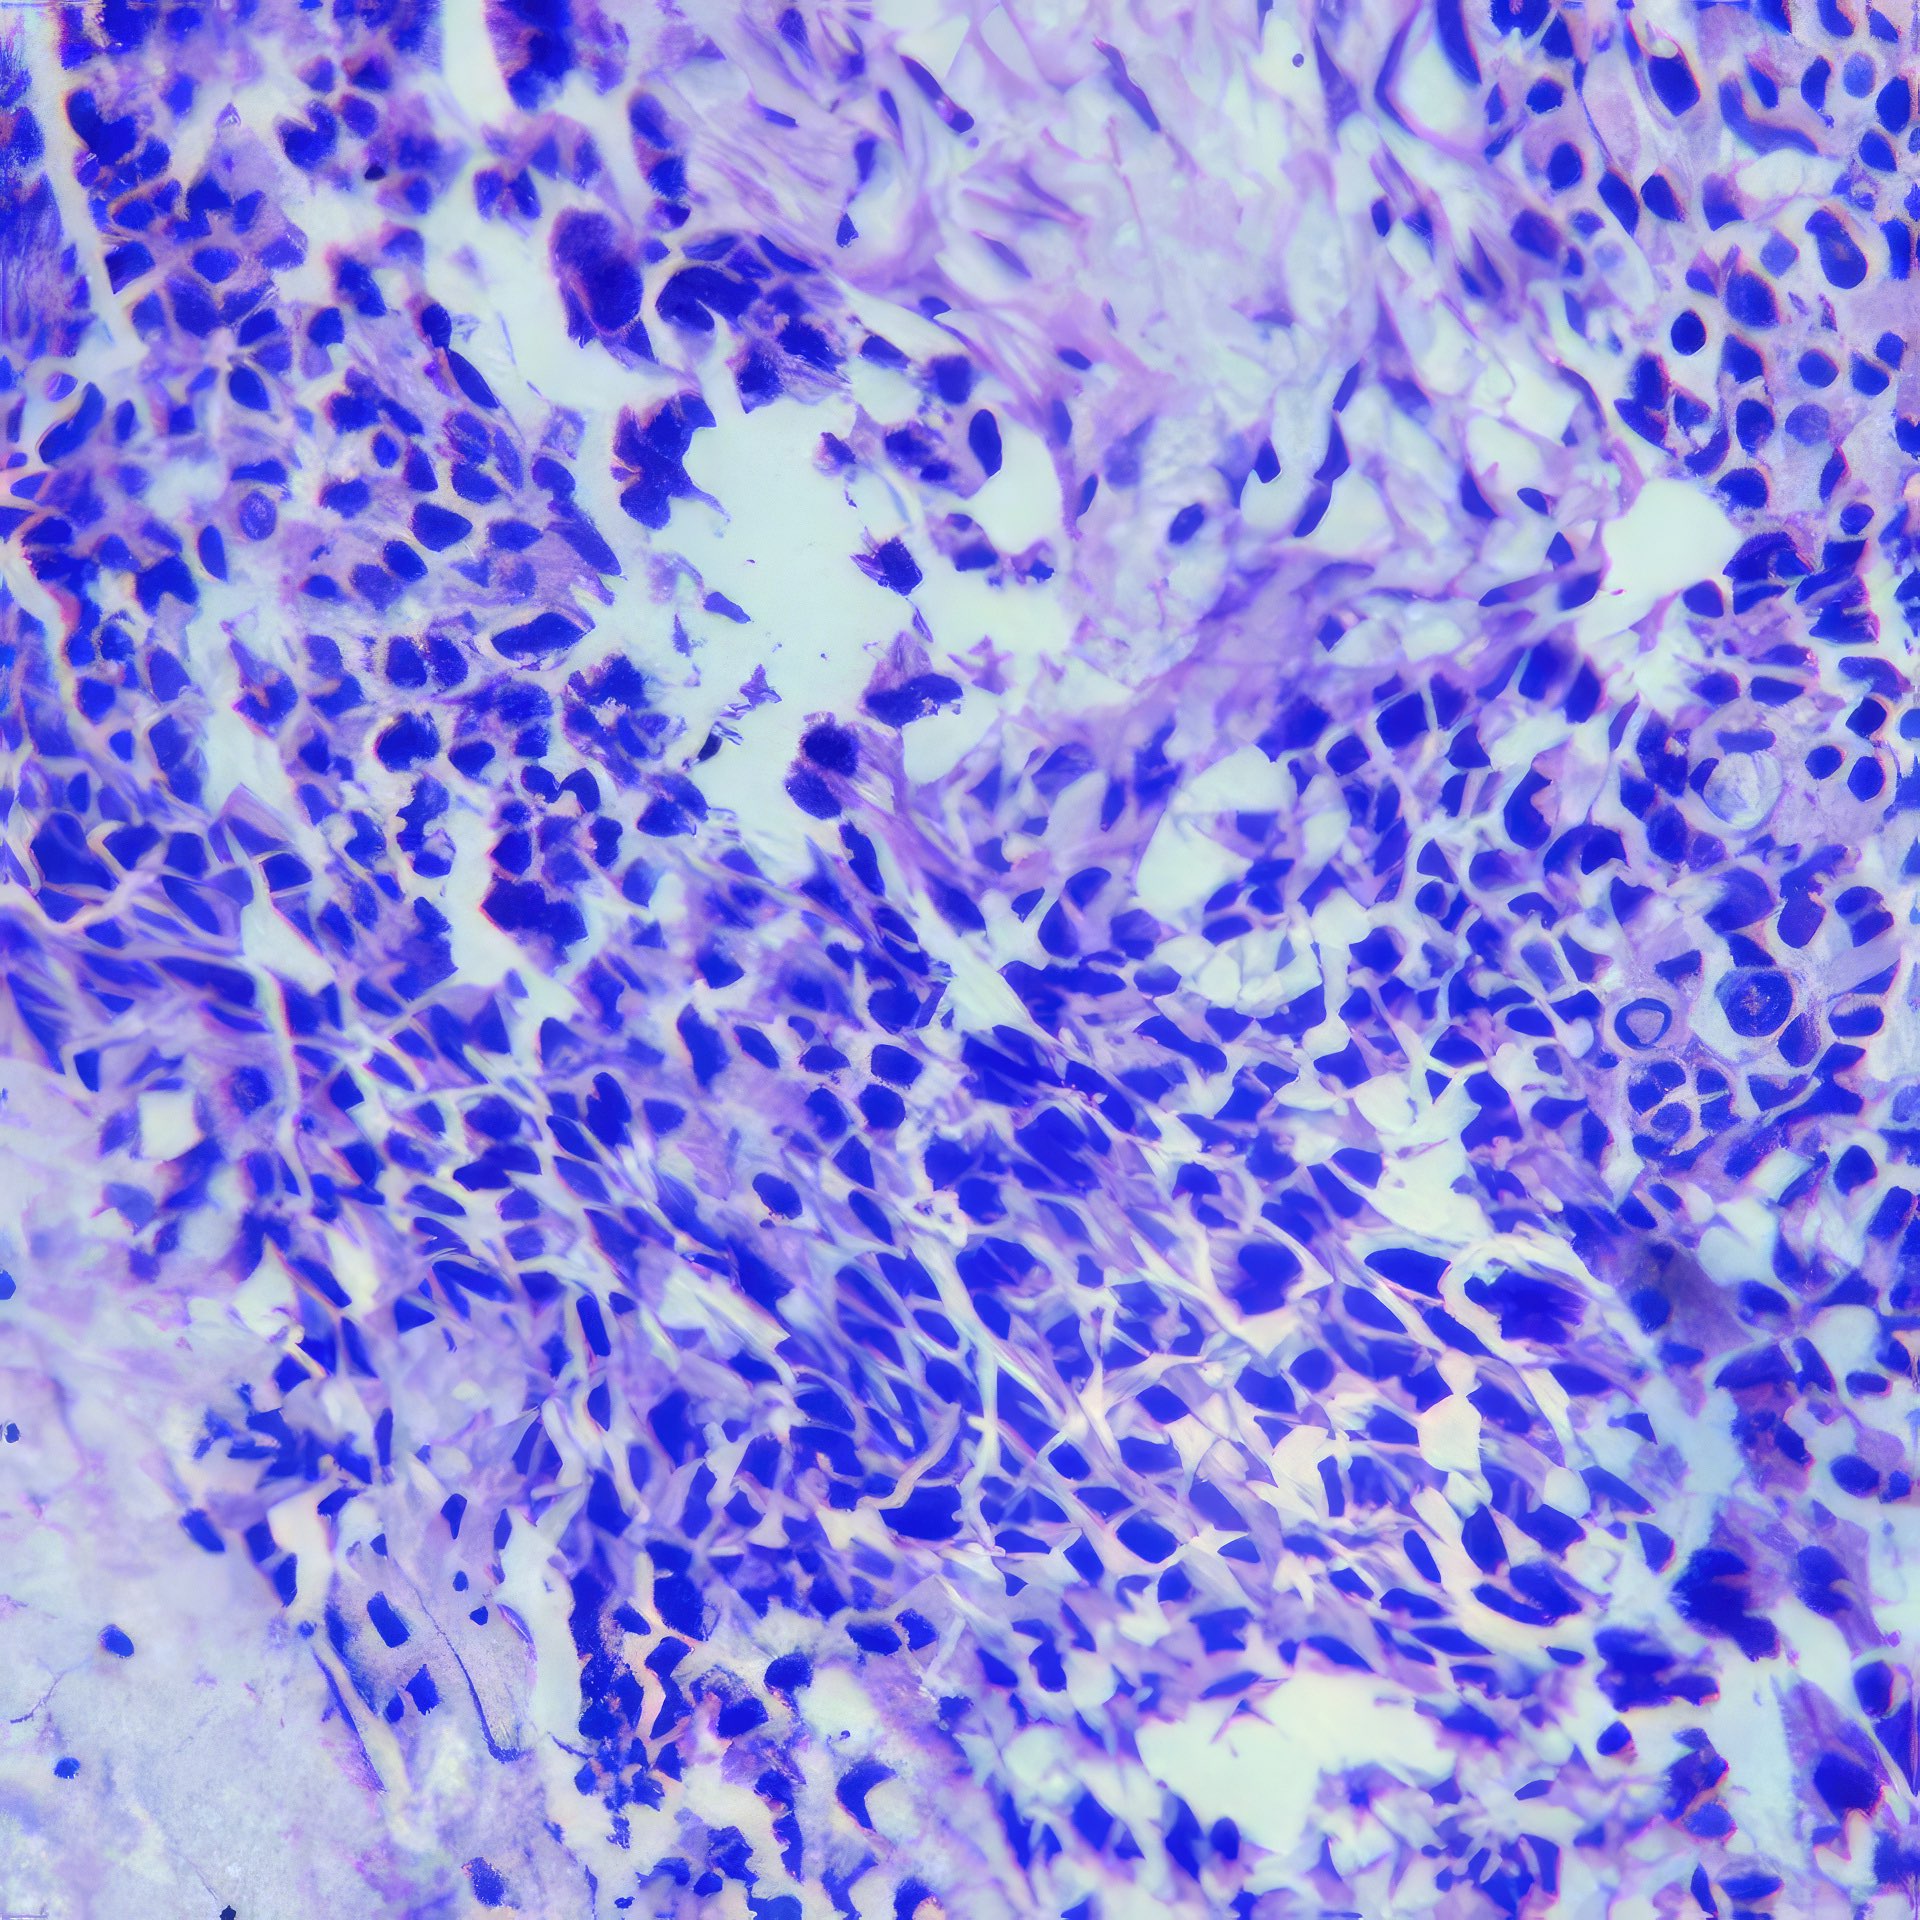

M, 55 Jahre, bemerkte seit 3 Monaten eine zunehmende inguinale Lymphknotenschwellung, der größte 3 x 4 cm messend, davon Feinnadelaspiration (FNA). Abbildung 1 bis 4: Verschiedene Areale des zytologischen Ausstrichs. Orig. 63x

Metastase eine malignen Melanoms

Die Bilder zeigen hochatypische Zellen. Deren überwiegend runde, teils auch ovalen Kerne variieren erheblich in ihrer Größe, sind deutlich grob strukturiert und enthalten meist ein oder mehrere prominente Nukleolen bzw. Chromozentren. Das Zytoplasma erscheint fragil. In jedem Bild finden sich auch Zellen mit pigmentbeladenem Zytoplasma. Der Ausstrichhintergrund enthält Blut und Zelldetritus, ebenfalls vermischt mit Pigmentkörnchen.

Der Patient beobachtete seit einem Jahr am Fuß eine pigmentierte Veränderung, die seit 3 Monaten auf 3 cm Durchmesser zunahm. Die prominente Atypie und die pigmenthaltigen Zellen sowie die ausgedehnte Metastasierung in die inguinalen Lymphknoten sind typisch für das Melanom. Eine Verwechslung des Melanin-Pigments mit Hämosiderin ist wegen der Zellatypie so gut wie ausgeschlossen. – Amelanotische Melanome zeigen oft eine weniger ausgeprägte Kernatypie und sind eher mit einem anderen Tumor zu verwechseln.